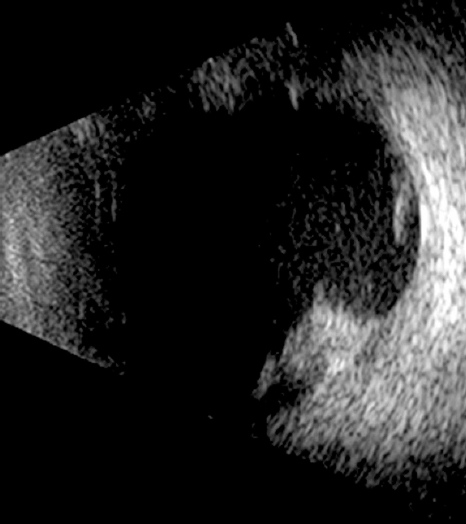

Рис. 6. Пациентка Е, 38 лет. Ультразвуковая B-сканограмма витреальной полости правого глаза после завершения силиконовой тампонады. Остатки пролиферативной ткани и преретинальных сгустков крови в центральных отделах и на периферии.